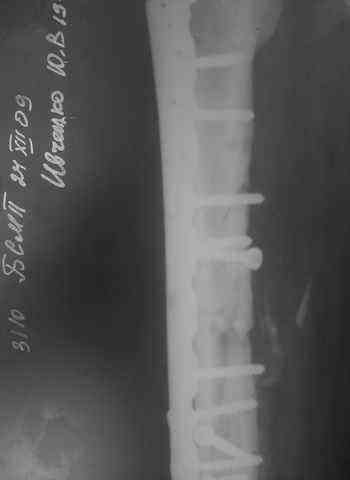

[Ortho] Несрошийся открытый фрагментарный,оскольчатый,перелом в/с/3 правого бедра

Несрошийся открытый     фрагментарный,оскольчатый,перелом в/с/3 правого бедра с размозжением мягких тканей.

Состояние после ПХО,МОС,ВО ЧКФ стержневым АВФ.

Операция:16.12.09,открытый накостный МОС,аутокостная пластика(из крыла подвздошной кости)правого

бедра.После п/о периоде заживление раны вторичным натяжением(на 5-е

сутки распущены швы, после очищения раны наложины вторичные швы)

На этапных RO-гр:остеолизис костного трансплантата и дистального фрагмента перелома

бедра.